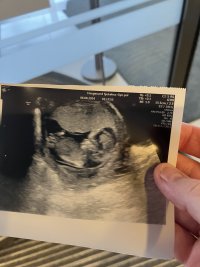

Jente!Alt bra med lille Jordmor mente 60 % sjans for jente Hva tror dere?? 13+0

JenteAlt bra med lilleJordmor mente 60 % sjans for jente

Hva tror dere?? 13+0